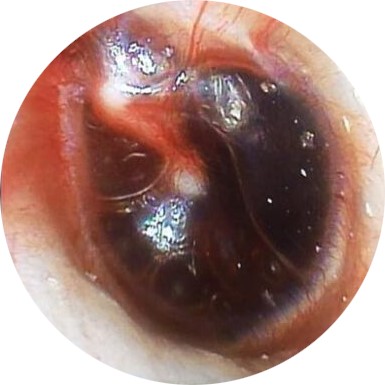

| TEED 3 |

Diffuse redness and retraction of tympanic membrane, plus gross hemorrhage within the tympanic membrane. |

|